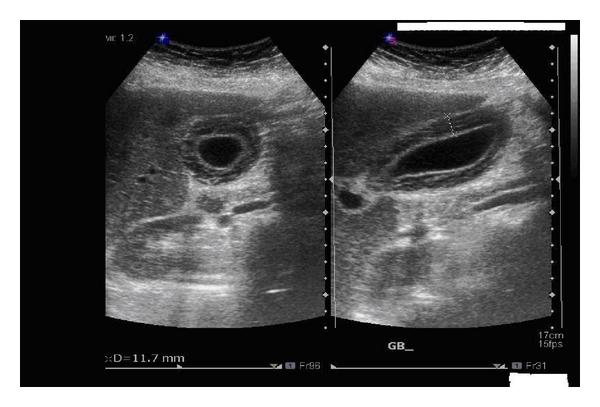

Mirizzi SYndrome

impacted stone in the cystic duct or GB neck

presence of two tubular structures representing the bile duct above the level of the cystic duct

Mirizzi SYndrome

impacted stone in the cystic duct or GB neck

presence of two tubular structures representing the bile duct above the level of the cystic duct